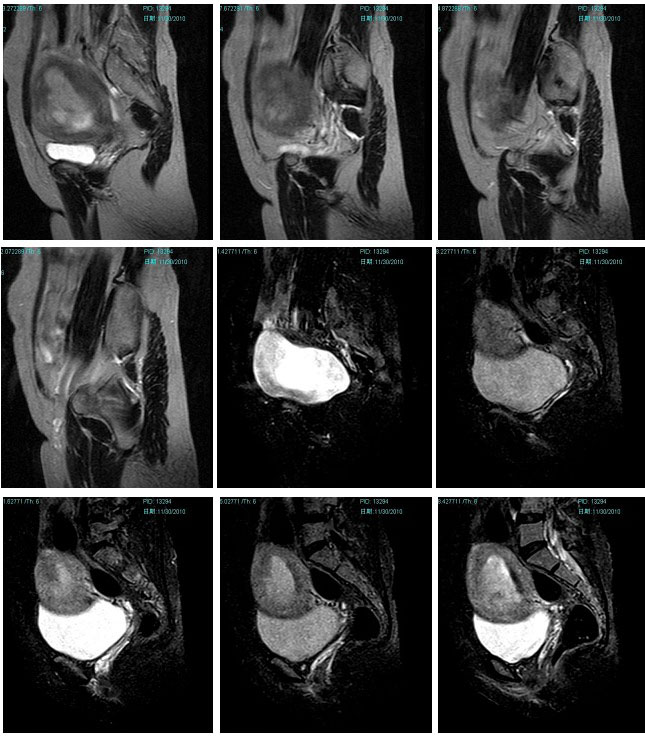

子宫恶性中胚叶混合瘤(癌肉瘤)

女性患者,52岁,月经量大,间断下腹痛一年余。多考虑:1:子宫前壁肌瘤。2:子宫内膜癌可能性大。已取活检,病理结果过几天出来。各位高手先讨论讨论。

子宫内膜太厚,结合带不完整,考虑内膜癌,建议刮宫病检。

宫内膜太厚,结合带不完整,考虑内膜癌,建议刮宫病检。

子宫内膜太厚,结合带不完整,考虑内膜癌,建议刮宫病检。支持!

术后病理结果出来啦!